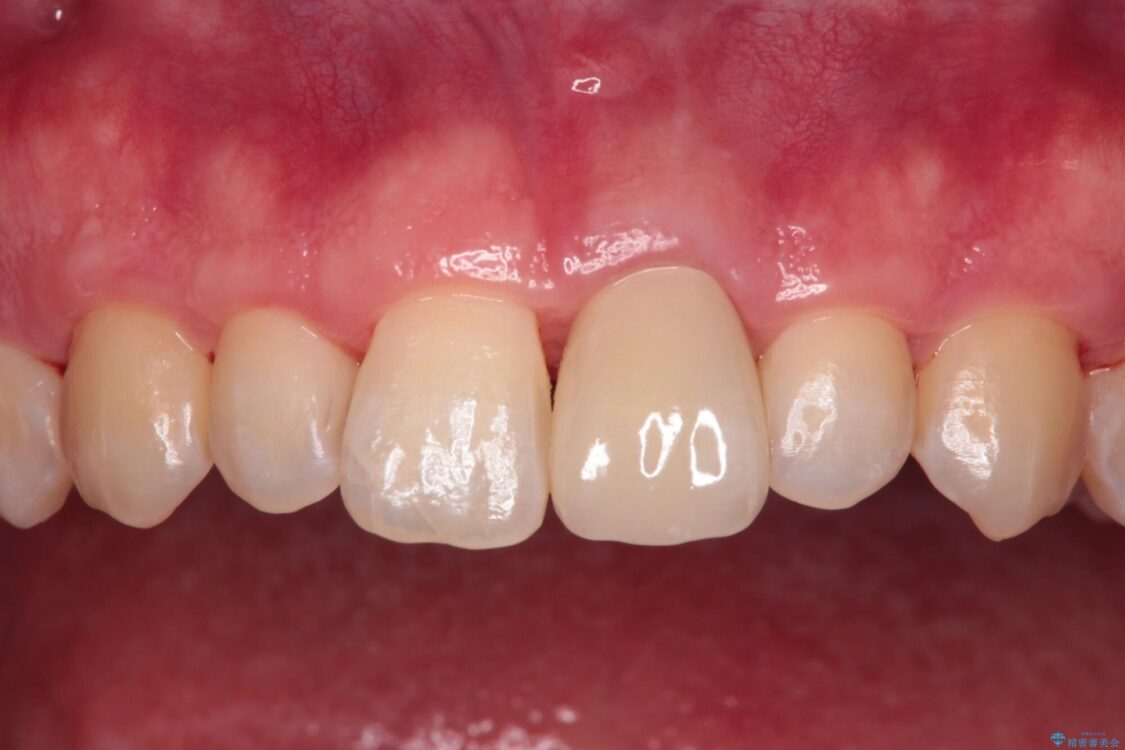

神経を取り除いた歯は時間とともに変色してきます。

クリーニングやホワイトニングでは改善できないため、オールセラミッククラウンなどによる補綴治療が必要となります。

治療後

• 変色した前歯をオールセラミッククラウンに 治療後画像